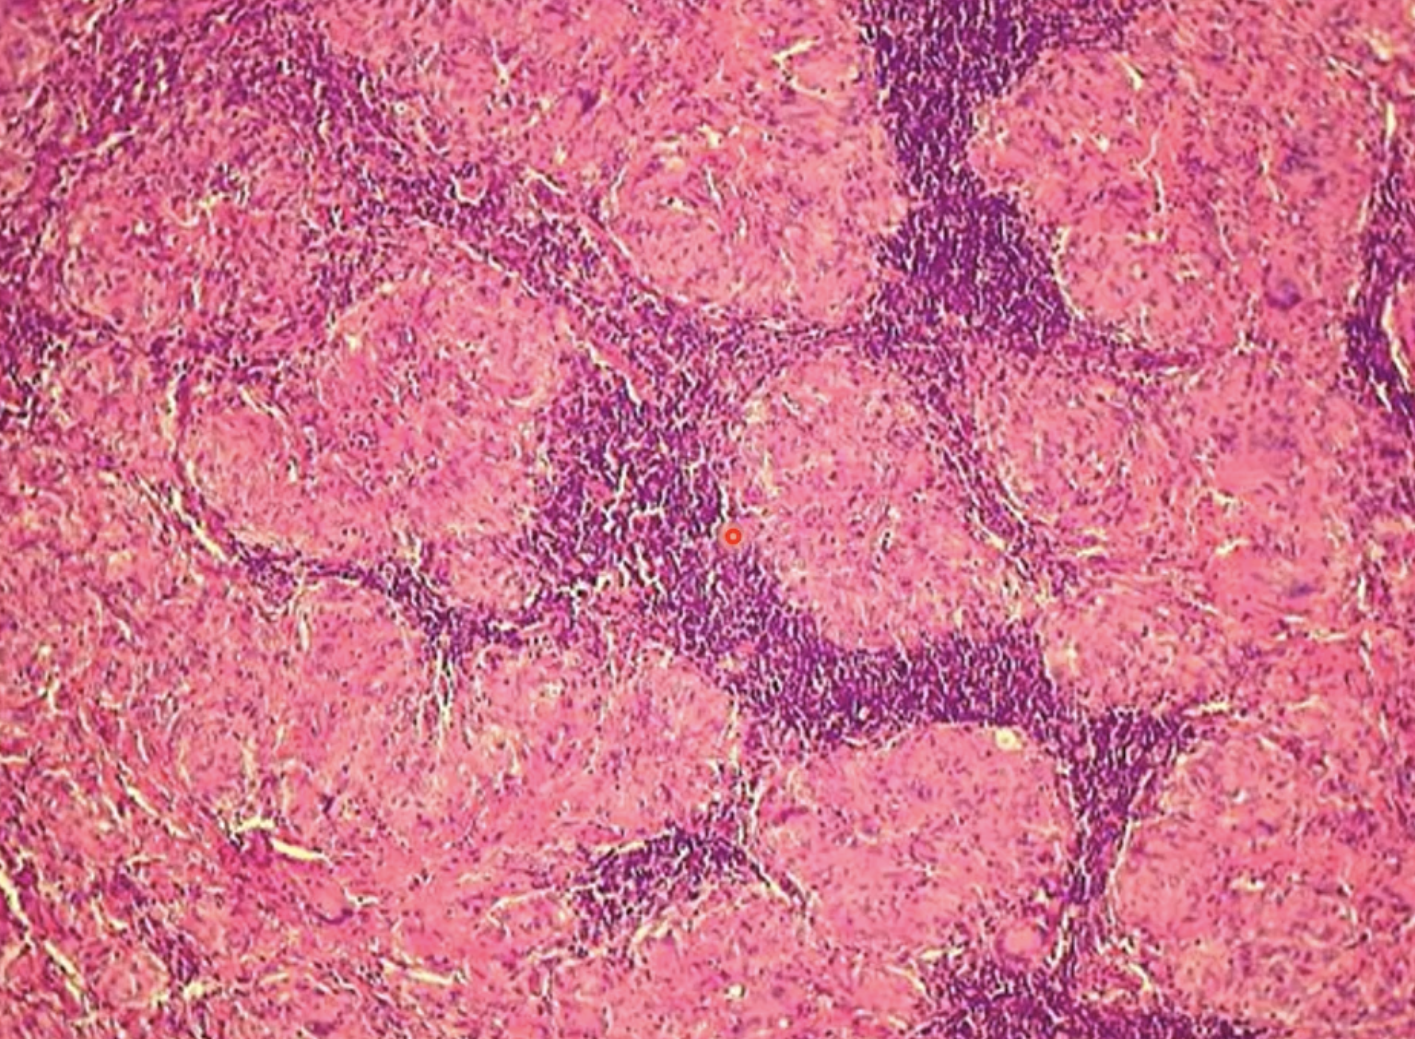

with the microscopic appearance of caseous necrosis, dead cells persist as

amorphous, coarsely, granular eosinophilic debris

with the microscopic appearance of caseous necrosis, necrotic cells do not

retain cellular outline

undergo complete dissolution

the microscopic appearance of caseous necrosis is frequently associated with

granulomatous inflammation and thick outer fibrous capsule

lymphoid effaced by cheese-like material - caseous necrosis

large glomerulations of macrophages - caseous necrosis